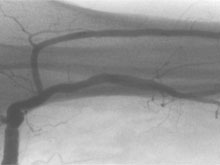

Seitenäste werden entweder über kleine Schnitte freigelegt und umstochen oder unter Sicht durch ein Gefäßendoskop embolisiert.